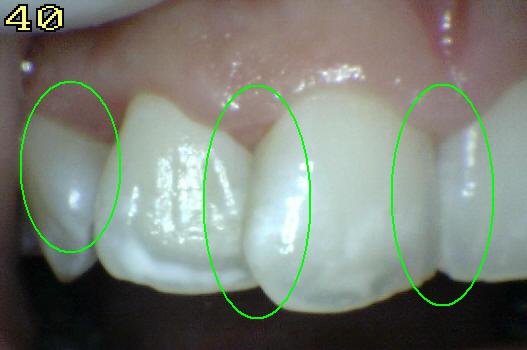

Código 4

(Caries Moderada): Sombra oscura

de dentina subyacente al esmalte intacto con o sin interrupción

localizada del esmalte

-

Esta lesión aparece como una sombra de decoloración

visible a través de una superficie de esmalte intacta, la que puede o no mostrar signos

de descomposición localizada del esmalte, como la microcavidad y /o discontinuida

< 0,5mm. después del secado con aire durante 5

segundos

La aparición de

la sombra se ve a menudo con más facilidad cuando

el diente está húmedo. El área oscura es una

sombra intrínseca que puede aparecer gris, negro-azul o

marrón-anaranjado,

a través de las paredes del esmalte vestibular, lingual o

palatino